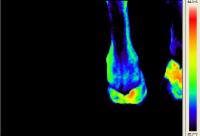

Walzertraum - Pferd nach Sehnen-OP - Horse after tendon operation